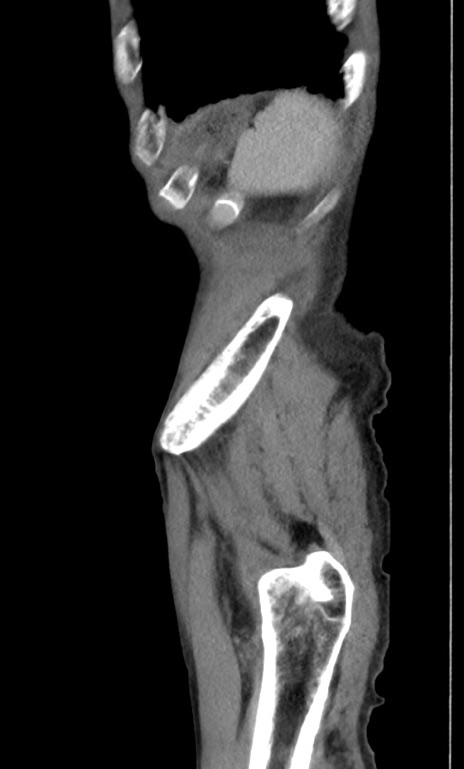

症例3(矢状断像)

【症例】 70歳代男性

【主訴】右鼠径部腫瘤、疼痛

【現病歴】本日朝より上記主訴あり、受診。

【既往歴】膀胱癌にて膀胱全摘、両側尿管皮膚瘻

【データ】WBC 5600、CRP 0.56